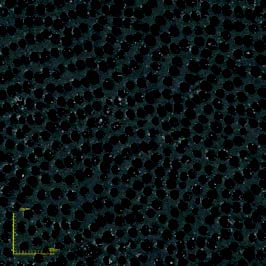

The OLS4000 allows the creation of high-resolution 3D images and requires no pretreatment or vacuum conditions of the sample. Thus, these images may be used for other analyses or even the continuation of an experiment. Captured images allow the observation of surface changes such as enamel prisms, dentin tubules, and eroded areas (Figure 2, 3, and 4, respectively).

Figures 3a and 3b: Dentin exposed to hydrochloric acid. 3a left side: Eroded dentin; 3a right side: Control area.

3b: Dentinal tubule exposition.